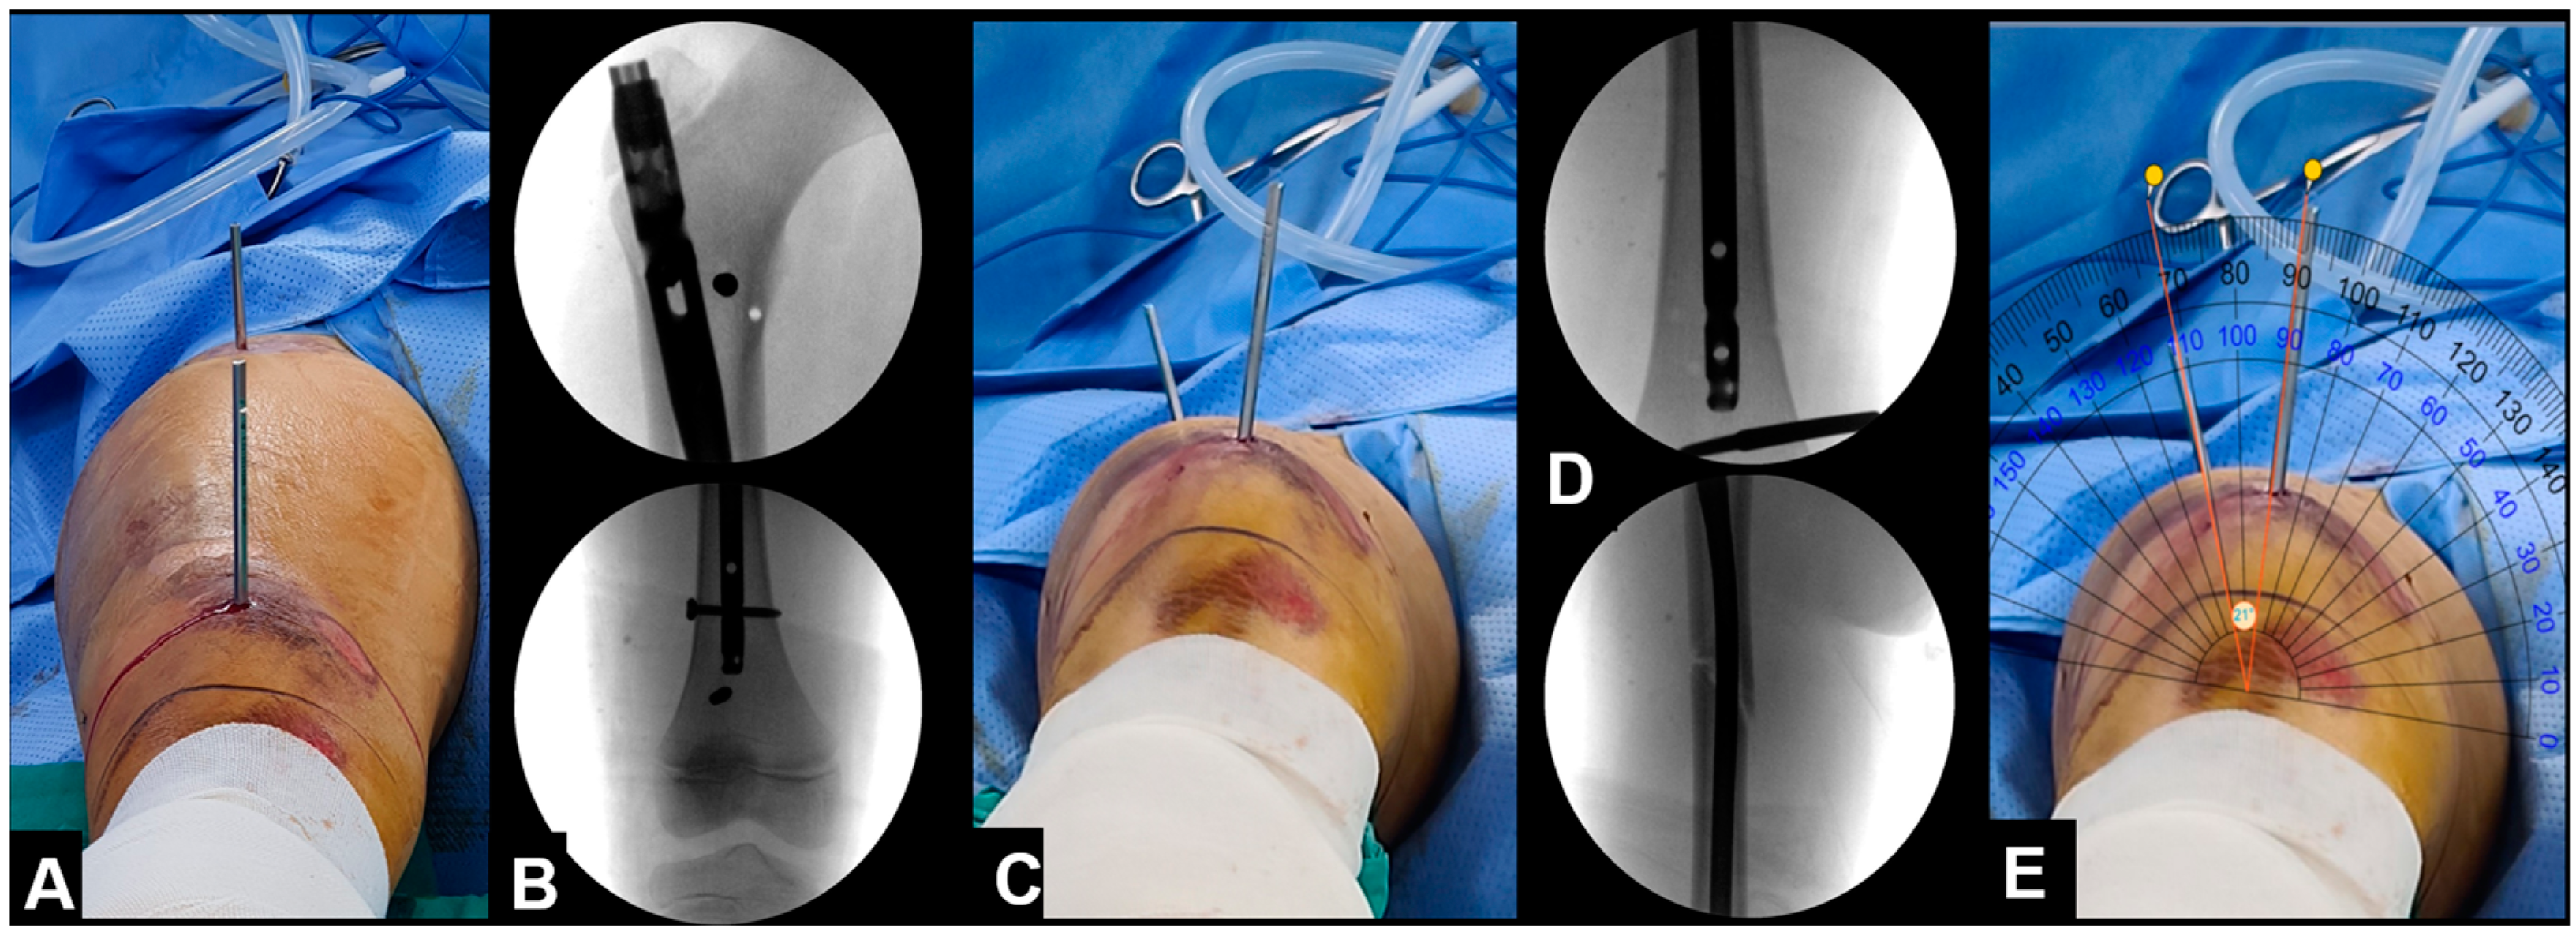

2.1. Surgical Technique

2.2. Smart Phone Application